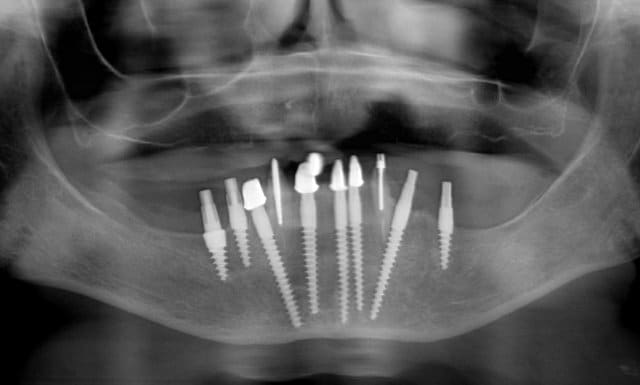

> feriez-vous le même traitement a un patient de 30 ans???

> problèmes de distance inter-implants

Pour un patient de 30 ans, pourquoi pas.Mais on peut implanter seulement 6 à 8 pour une prothèse fixée.Et 4 implants pour une prothèse amovible dans la mandibula.

Pour la distance inter-implants c est une bonne remarque, le distance réglementaire est de 2/3mm en méthode conventionelle , ici c´est une variante du flapless en forant de manière à condenser l´os via un foret à 3 faces. En préservant le périoste on a remarqué que cette distance réglementaire pouvait être plus petite. C est une observation , qui marche (en flaples) dans ma pratique et dans celles de mes confrères Allemands, à ma connaissance pas enormément documenté . Ceci dit il y a un livre en francais qui en parle "implantologie flapless" de Byung Ho Choi et wilfried Engelke (Pr de Göttingen).

Sur le cas posté au début la dernière radio est après deux ans post OP. Ci dessous un autre exemple.

Les 12 premières photos sont un même cas avec implantation immédiate.

Le deuxième cas c est les photos 13 14 15 , (la photo 14 et 15 est après 5 ans)

Le dernier cas (3 dernieres photos), a été realisé il y a 5 ans il n y a pas de problème, je ne trouve pas les radios malheureusement je vais chercher encore un peu dans la journée.

46 : 10mm de longueur et 4,5mm de diamètre (parce que je n ai pas atteint la stabilité primaire avec le condenseur 3,0 la mesure 30Ncm)

45 et 36: 10mm de longueur et 3,5mm de diamètre

44, 42, 31 et 34 : 22 mm de longueur et 3,5 mm de diamètre

32 : 20 mm de longueur et 3,5 mm de diamètre

ton commentaire m a fait remarqué que je n´ ai pas mis la photo de la prothèse du cas! merci ! :-)